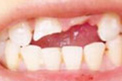

适应症状

• 牙齿缺损

• 间隙牙

• 畸形牙

• 牙釉质发育不全